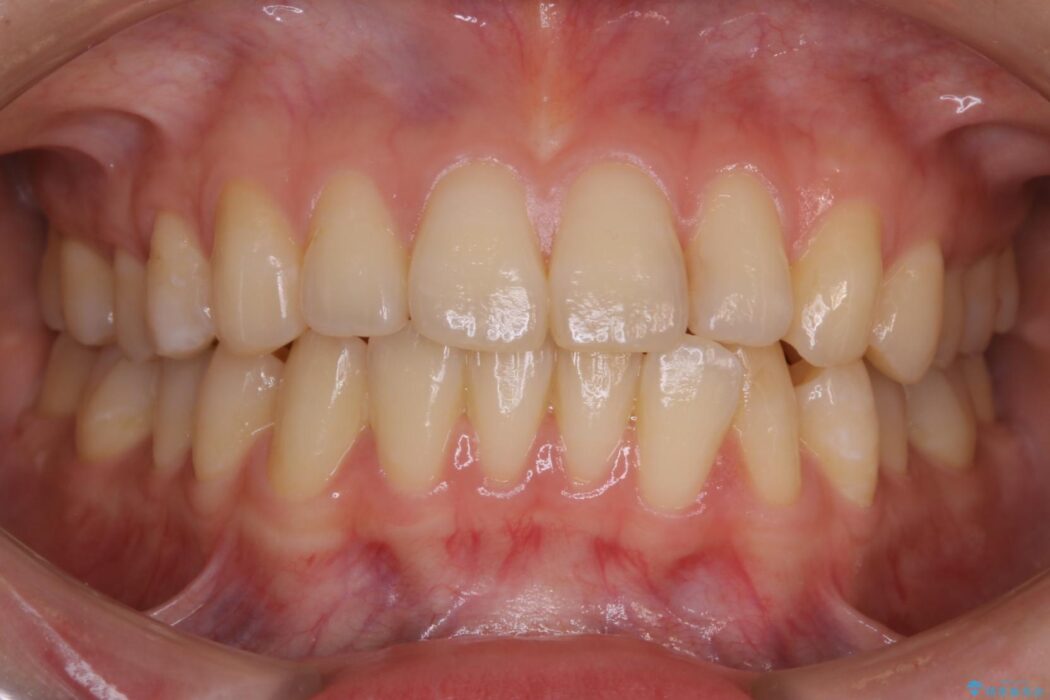

下額前歯が少しガタついていることを気にされて来院されました。

検査をしたところ奥歯の噛み合わせなどに問題が見られなかったため、軽度のねじれがある下顎前歯に焦点を当てた部分矯正の適応が可能と判断し、インビザラインのライトパッケージをご提案しました。